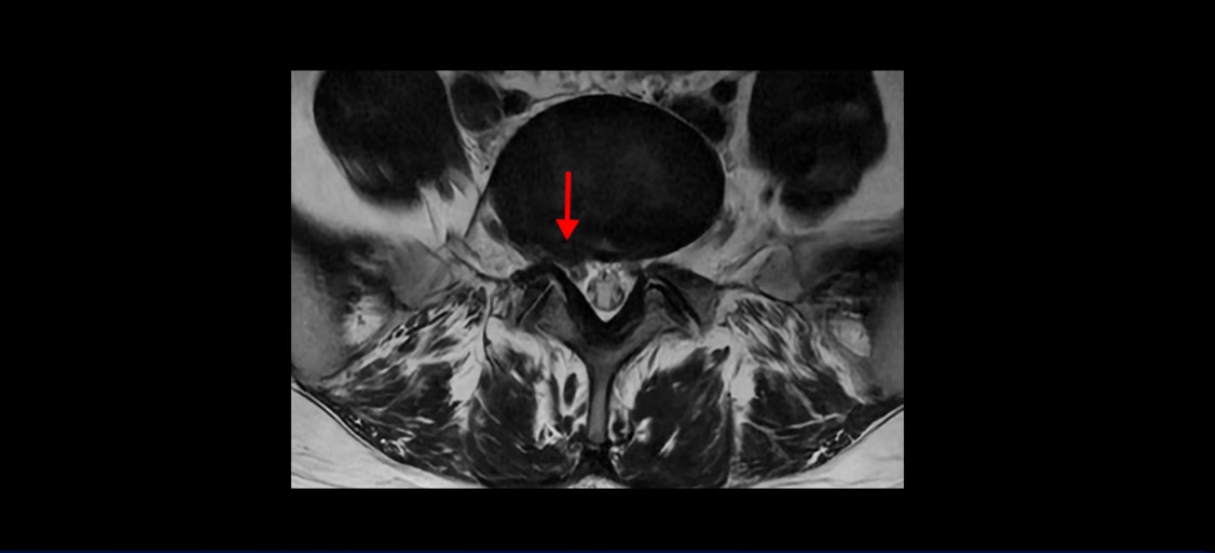

4번 5번과 3번 4번 마디도 디스크가 중앙으로 살짝 밀려나와있지만 최근에 섬유륜이 찢어진 것도 아니고, 신경 다발을 누를 정도로 심하게 밀려나와 있는 것도 전혀 아닙니다.

양쪽 신경 가지가 빠져나가는 추간공도 충분히 넓어서 신경학적 방사통을 일으킬 여지가 없습니다.